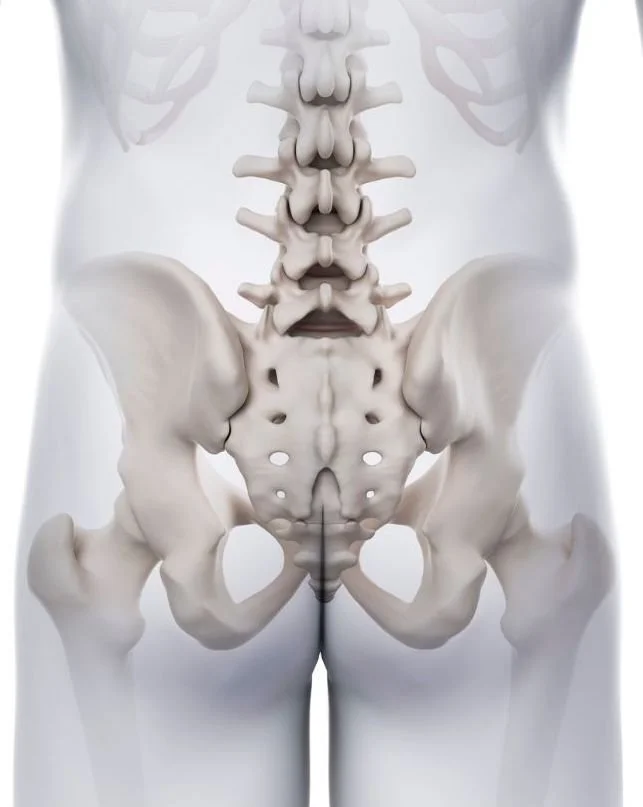

For those who like visualising things, the sacrum is wide at the top and narrow at the bottom. This triangular shape is… I want to say ‘snuggled’… but no, there is nothing cosy about it. It’s quite literally ‘wedged' between:

The lowest part of the lumbar spine - L5 vertebrae

The two ilium bones, i.e., the large bones at the side of your hips; and

The coccyx, also known as tailbone, located at the very end of the spine (more on that truly under-appreciated bone and its importance later).

Let’s start from the location. The name, as usual in anatomy, explains what connects to what. The sacroiliac joints link the 1st, 2nd, and top part of the 3rd segments of the sacrum to the iliac bones. This is sometimes poetically called ‘the wings of the pelvis.’